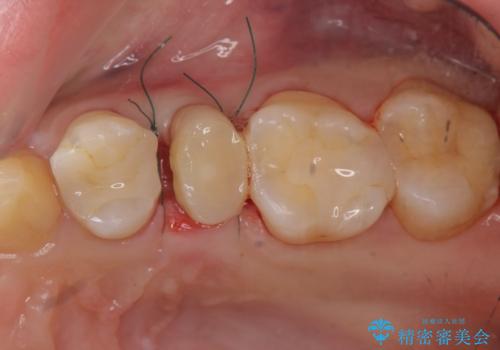

- 歯ぐきの腫れや、歯の内部が黒く見えることからの虫歯の治療を求めて来院されました。

虫歯が大きかったことから、神経の温存はできたものの歯ぐきよりも深い虫歯の問題を解決するため、部分矯正治療を併用したセラミック治療を行うこととしました。

当初、歯ぐきよりも深い虫歯の存在や、歯のポジションに問題がありましたがマルチブラケットを用いた部分矯正で行うことで歯の挺出同時に適切な位置へと歯を移動させ、歯周環境を整えたセラミック治療を行うことができました。